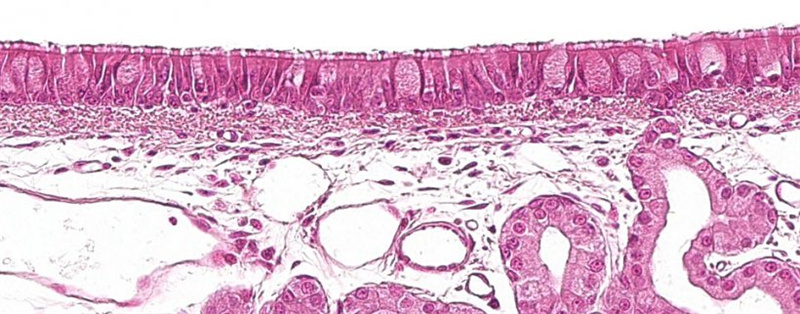

ÖíºôÎüµÀð¤Ä¤

ËùÓÐճĤÉÏÆ¤×éÖ¯£¨Ö÷ÒªÊÇÏû»¯µÀ/ºôÎüµÀ£©¹ÌÓвãÖж¼ÓоÞÊÉϸ°ûºÍ µ¥ºËϸ°û¡£µ±Õ³Ä¤ÉÏÆ¤×éÖ¯ÆÆËðʱ£¬¾ÞÊÉϸ°û»á´óÁ¿¾Û¼¯£¬Ó벡¶¾Ö±½Ó½Ó´¥¡£